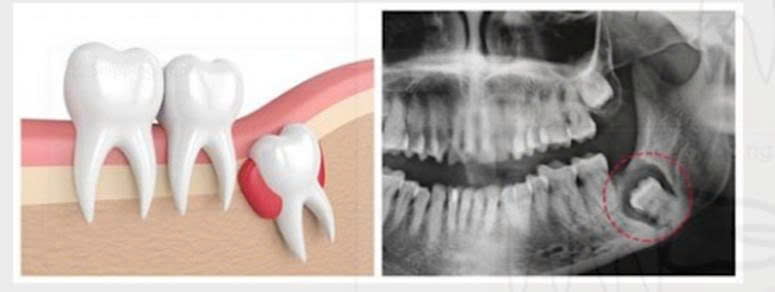

3.5. Tiêu chân răng lân cận dẫn tới phá hủy cấu trúc răng

Sự tiêu chân răng xuất hiện ở những răng phía sau của hàm trên và hàm dưới, bắt đầu là sự tiêu chân răng phía xa, dần dần gây phá hủy toàn bộ cấu trúc răng.

Hình 8. Răng khôn hàm dưới mọc lệch gây tiêu chân răng hàm lớn thứ hai

Đôi khi, răng khôn ngầm hàm trên ở vị trí quá cao, có thể gây thủng, viêm xoang hàm hoặc răng khôn ngầm hàm dưới ở vị trí quá sâu, đè lên dây thần kinh răng dưới gây tê môi. Cần phẫu thuật nhổ răng khôn ngầm để loại bỏ nguyên nhân gây bệnh.

Hình 9. Thủng xoang hàm do răng khôn hàm trên – Răng khôn hàm dưới đè vào dây thần kinh răng dưới

3.6. Nang thân răng

Các răng ngầm trong xương có thể tạo nang thân răng tiến triển âm thầm trong xương hàm. Nếu không được điều trị, xương hàm sẽ bị tiêu xương dần dần, làm tăng nguy cơ gãy xương hàm.

Hình 10. Nang thân răng khôn hàm dưới trái (R38)